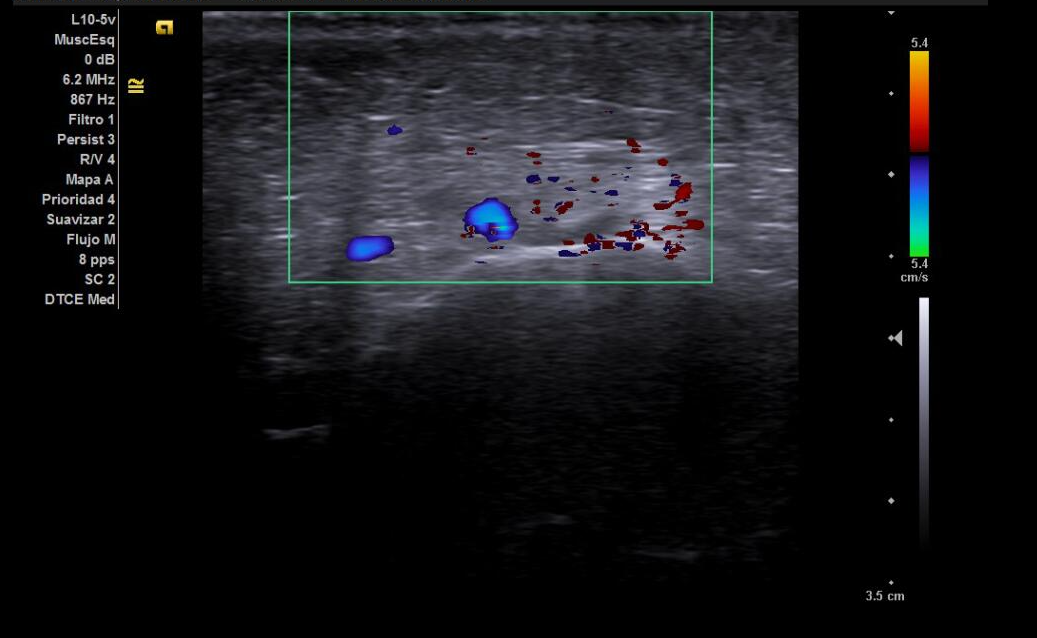

Hallazgos ecográficos

Tendones supra e infraespinoso normales; bursa fina; cabeza larga del bíceps normal. Nervio supraescapular discretamente hipoecoico y engrosado en la escotadura; sin colecciones. Sin signos de pinzamiento dinámico.

Analgesia, relajantes musculares y fisioterapia. Ante la no mejoría, infiltración ecoguiada del nervio supraescapular (1 ml trigon + 4 cc anestésico local). Sin incidencias.